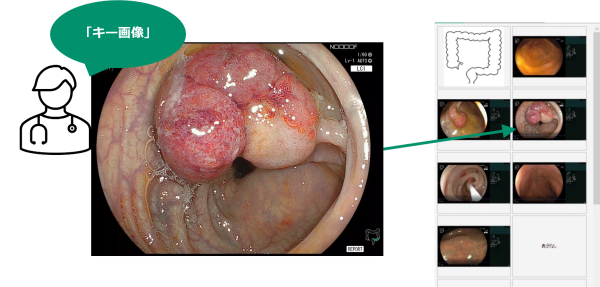

検査中に、レポートに貼付したい静止画像(キー画像)を音声操作で指示することができる。検査後にレポート記入画面を開くと、登録を指示した静止画像が貼付される。検査後に、撮影した大量の静止画像の中から、必要な画像を探す手間を削減する。

検査中にキー画像として登録指示した静止画像は、検査後にレポート記入画面を開くと既に貼付されている。貼付されている画像は、医師により追加、修正可能である。